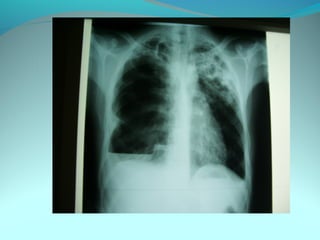

Image radiologique bilatirale a type d’opacité nodulaire occupant les

2/3 sup du poumon droit et la ½ sup du P G confluante par pour

former de grosses opacités

DIAGNOSTIC:

Tuberculose pulmonaire bilateral

Pneumonie bilaterale